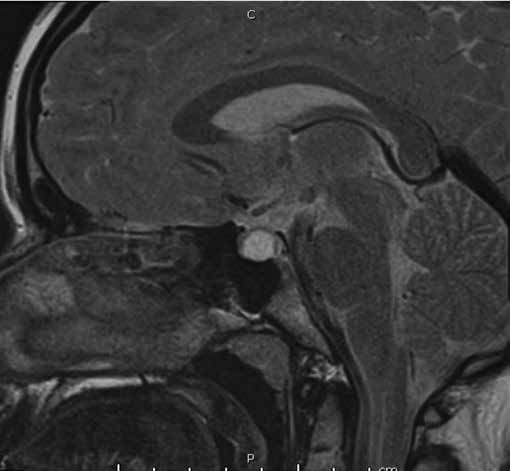

Figura 1b. RM de si a lla turca contrastada con gadolinio. Corte sagital en T2. Cortes 2.5 mm.

Se informa a continuación los estudios de imagen. Ecografía ginecológica (estudio previo indicado por ginecología): útero de forma y tamaño normal que mide 52 x 21 x 29 mm, endometrio de 5 mm, ovario derecho 25 x 18 mm, ovario izquierdo 28 x 17 mm. RM de silla turca: glándula hipofisaria aumentada de tamaño que mide 1,0 cm de altura, 1,9 cm de ancho, 1,2 cm anteroposterior, imagen de comportamiento quístico en las diferentes secuencias con realce homogéneo del parénquima glandular que rodea la lesión quística y se mantiene hipointensa en T1 (Figura 1a), tallo hipofisario en la línea media, quiasma óptico y estructuras vasculares sin compresión. En T2 se aprecia parénquima glandular hiperintenso (Figura 1b). Campo visual sin alteraciones.